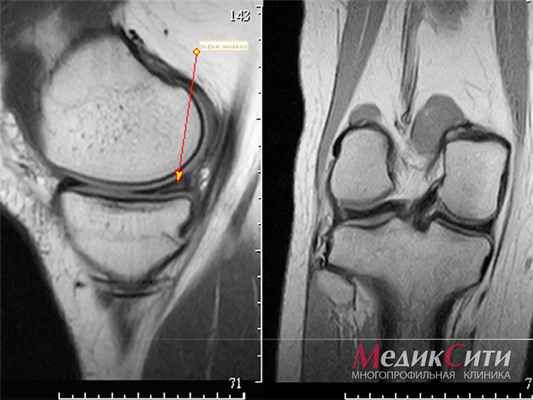

МРТ колена: норма

(Слева) При МРТ с контрастным усилением в сагиттальной плоскости на Т1ВИ в режиме FS определяется гетерогенное и достаточно интенсивное контрастирование выявленного образования. Небольшие очаги, соответствующие кальцитрикатам, неконтрастируются.

(Справа) При МРТ в аксиальной плоскости на Т1ВИ визуализируются инфильтративная структура и нечеткий контур кальцифицирующейся апоневротической фибромы. Образование прилежит к сухожилию сгибателя, что также характерно для гигантоклеточной опухоли и фибромы сухожильного влагалища. Однако перечисленные опухоли обычно имеют четкий контур.